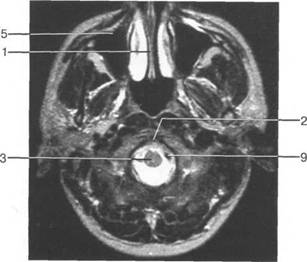

Следует отметить, что в настоящее время оптимальным методом исследования структур задней череп 13513u2010n 85;ой ямки является МРТ, которая, в отличие от КТ, лишена артефактов от кост

Следует остановиться на анатомии подпаутинных пространств задней череп 13513u2010n 85;ой ямки IV 20 мм. Между основанием череп 13513u2010n 72; и нижней поверхностью мозга от большого затылочного отверстия вдоль ската и спинки турецкого седла простирается задняя базальная цистерна. В зави IV

Следует остановиться на анатомии подпаутинных пространств задней череп 13513u2010n 85;ой ямки IV 20 мм. Между основанием череп 13513u2010n 72; и нижней поверхностью мозга от большого затылочного от IV